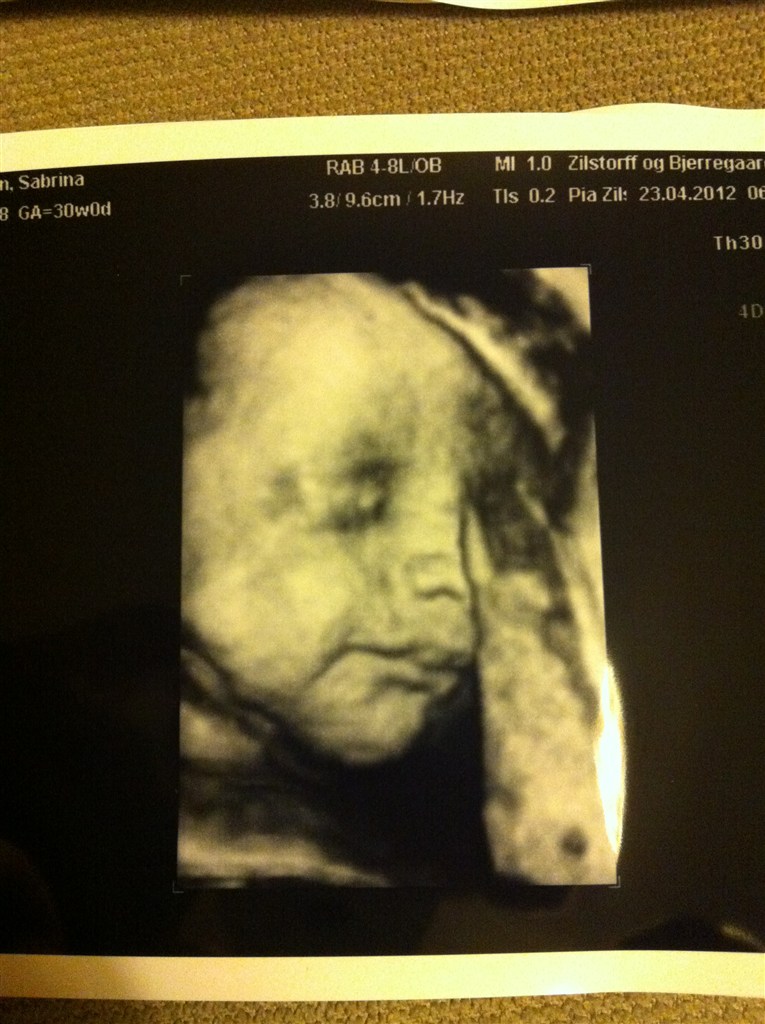

Jeg ved seriøst heller ikke hvad jeg skal med alle de billeder - tror jeg vil gøre som Michelle skrev tidligere, ligge dem i en kasse med andre ting fra graviditeten - og så kan vores datter få den når hun bliver stor